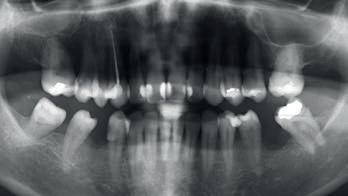

Na análise do sorriso apresentava os seguintes problemas: 1. Dentes superiores escuros e com manchas, principalmente o dente 21. 2. Restaurações em compósito com cárie subjacente, com infiltração marginal e discromia. 3. Curvatura da linha incisal invertida 4. Arcada em forma de “V” numa vista oclusal 5. Corredores vestibulares pouco preenchidos 6. Mordida cruzada de todos os dentes do 2º quadrante 7. Festonado gengival desalinhado (11, 21, 22 e 23 elevados)

Apresentava também: 1. Ausência dos dentes 45a1 e 36 2. Migração para distal do 45 3. Mesioinclinação dos 45, 47 e 37 4. Recessão gengival do 31

Após a realização de ortopantomografia, telerradiografia e estudo ortodôntico, foi proposta disjunção maxilar cirúrgica e tratamento ortodôntico para descruzamento de mordida e restante correção da posição dos dentes, mas a paciente recusou.